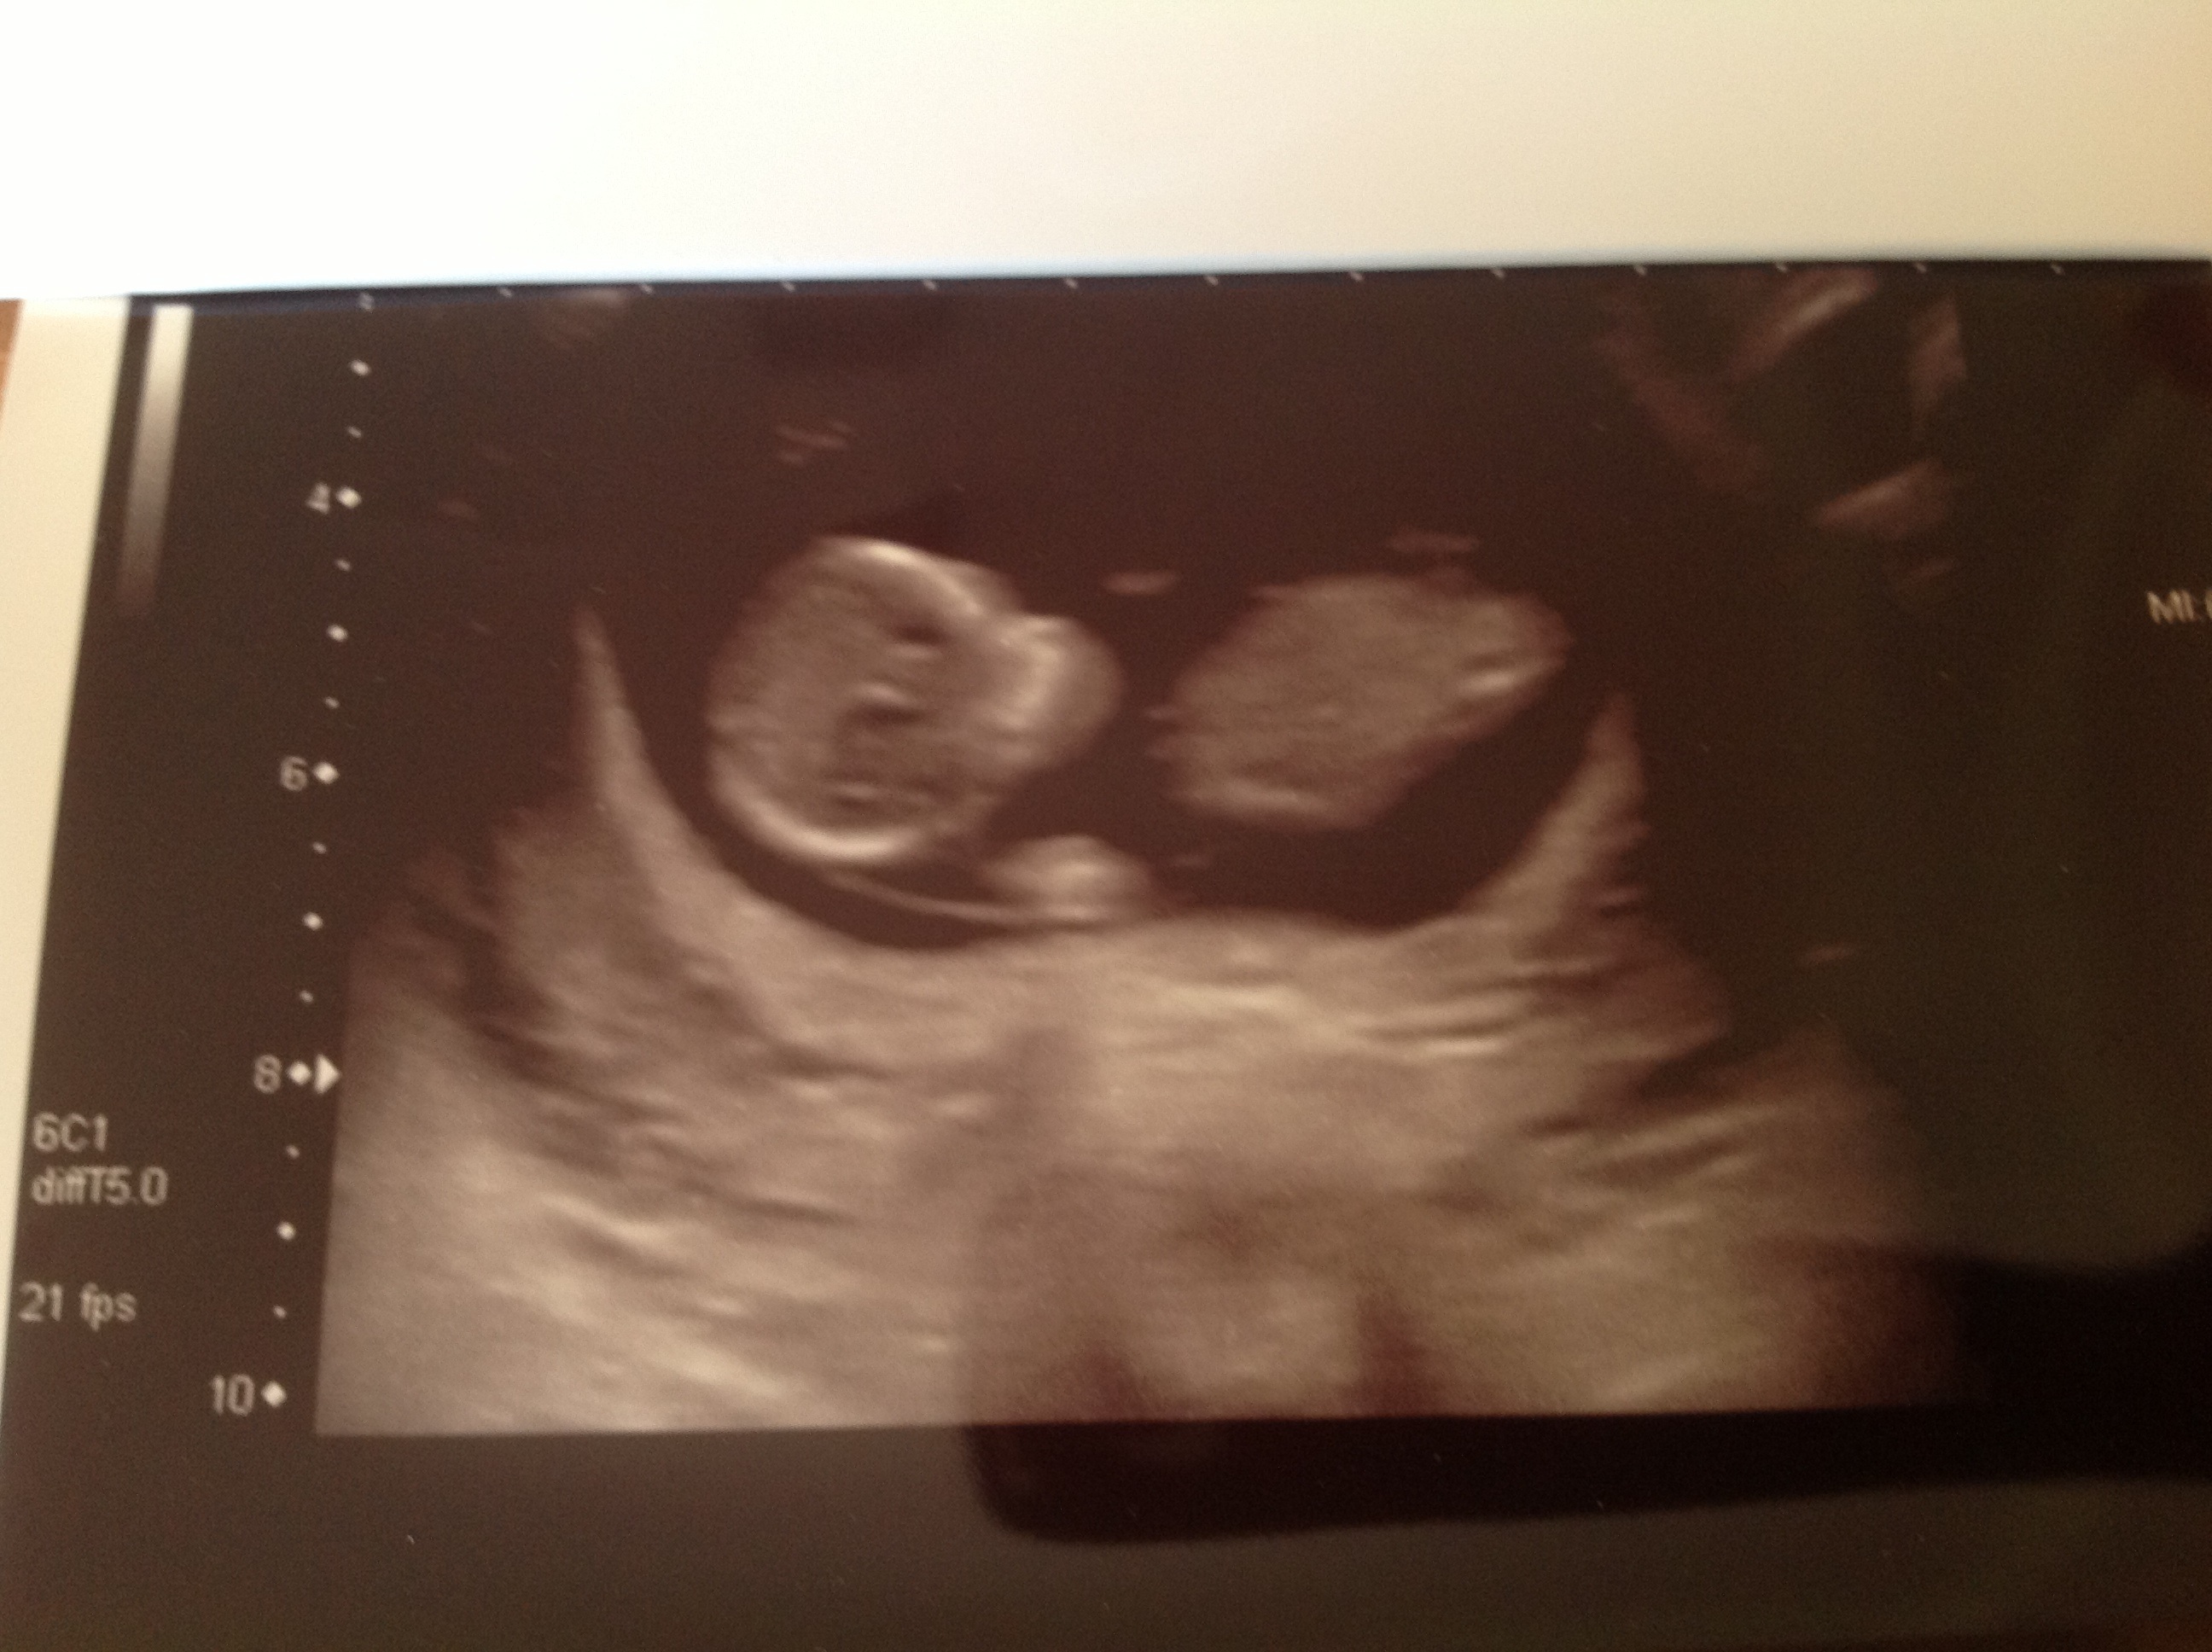

The latest scan was 12 weeks, 5 days and they gave me the last picture. I'm sure I can see a willy! But, not sure if its in the right place or the correct angle for this age? I asked the sonographer and she said she couldn't tell, but it could be a leg that only partially showed for the picture. Is this the nub?

12weeks 5 days is next one.

Attachment 12285